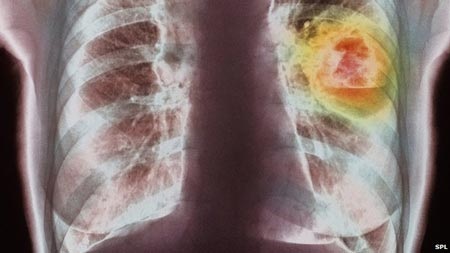

Ung thư phổi, loại ung thư có nguyên nhân chính từ việc hút thuốc lá, là bệnh ung thư phổ biến nhất trên toàn cầu, với 1,8 triệu trường hợp chiếm khoảng 13% tổng số các loại ung thư.